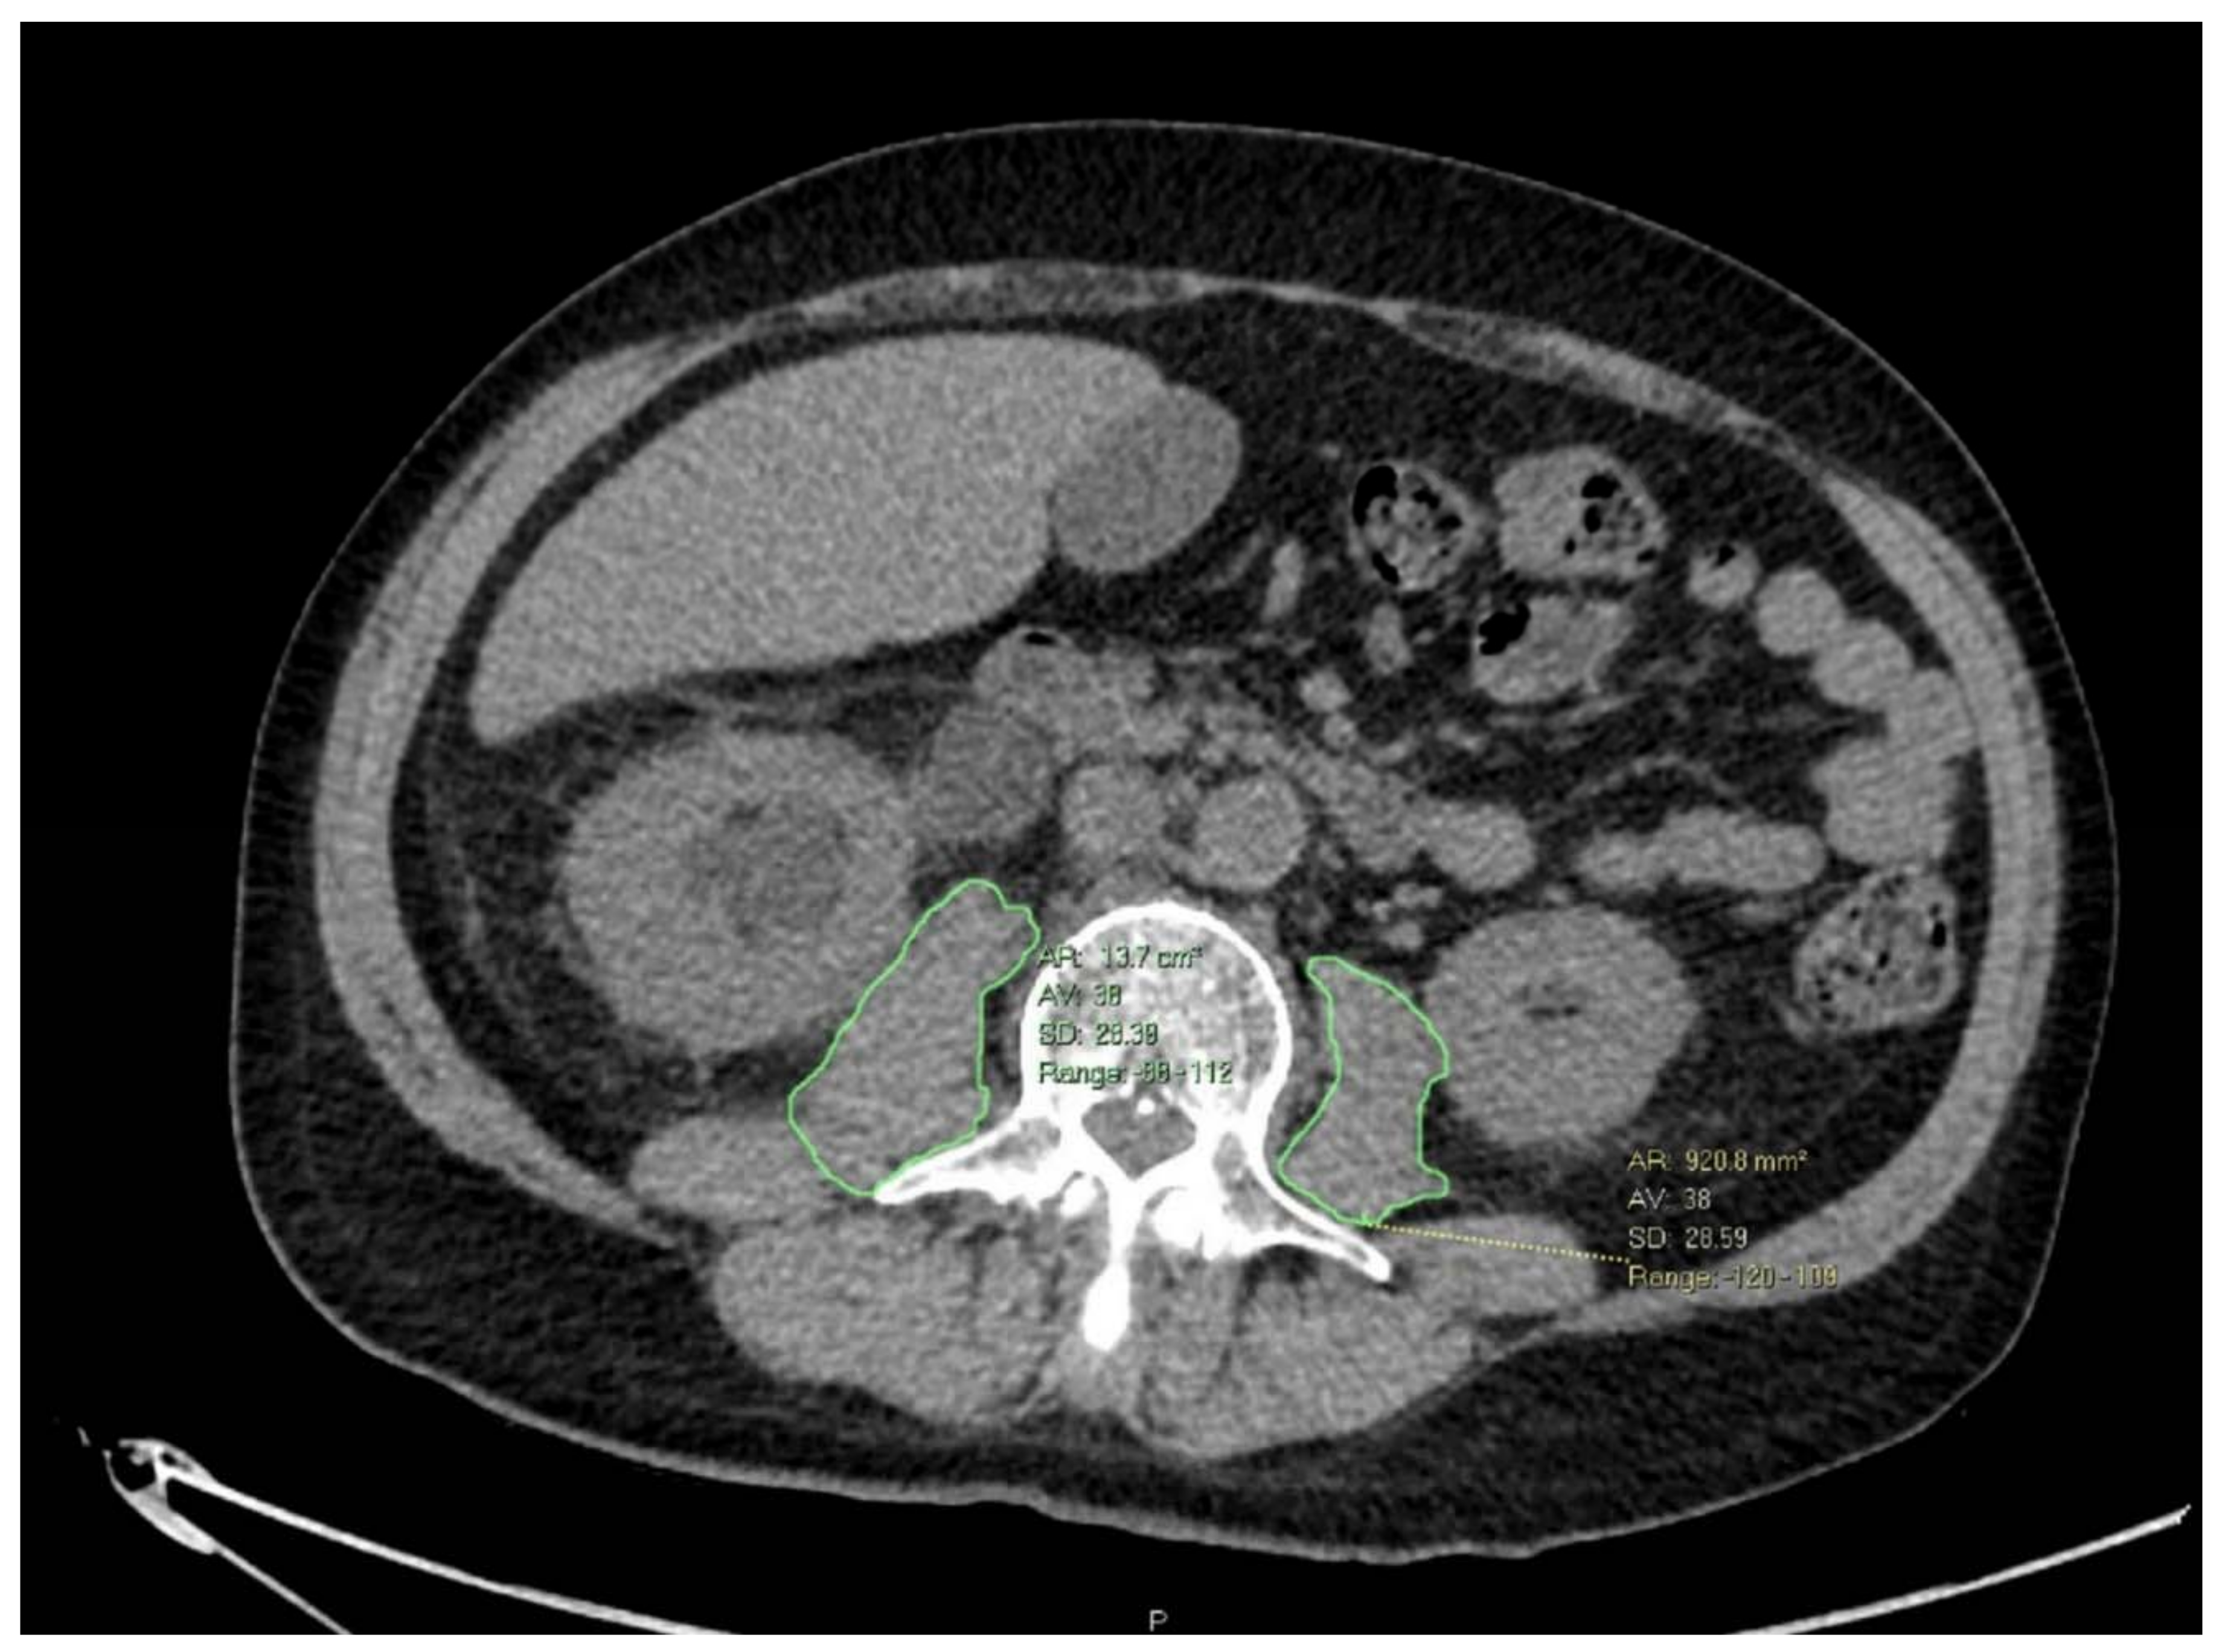

| Pre NAC SMI [cm2/m2] | 6.96 (5.73, 8.33) |

| Post-NAC SMI [cm2/m2] | 6.17 (4.97, 7.40) |

| SMI change [cm2/m2] | −0.71 (−1.58, −0.06) |

| Pre NAC SMI [cm2/m2] | 6.64 (5.59, 7.35) | 7.23 (5.95, 8.66) | 0.045 | 6.79 (5.61, 7.50) | 7.70 (6.46, 8.96) | 0.031 |

| Post-NAC SMI [cm2/m2] | 6.30 (5.53, 7.08) | 6.04 (4.91, 7.64) | >0.9 | 6.14 (5.15, 7.16) | 6.38 (4.81, 7.58) | >0.9 |

| SMI change [cm2/m2] | −0.11 (−0.41, 0.1) | −1.2 (−1.72, −0.34) | <0.001 | −0.27 (−0.99, 0.08) | −1.50 (−2.00, −0.76) | <0.001 |

| SMI change [cm2/m2] | −0.30 (−1.10, 0.01) | −1.50 (−2.00, −0.91) | <0.001 | −0.30 (−1.05, 0.07) | −1.58 (−2.03, −0.68) | <0.001 |

| SMI change | 0.26 | 0.12, 0.49 | <0.001 | 0.28 | 0.15, 0.48 | <0.001 | 0.37 | 0.21, 0.61 | <0.001 | 0.29 | 0.15, 0.49 | <0.001 |

| SMI change | 0.31 | 0.12, 0.72 | 0.039 | 0.34 | 0.13, 0.79 | 0.045 | 0.4 | 0.2, 0.71 | 0.004 | 0.2 | 0.07, 0.49 | 0.001 |